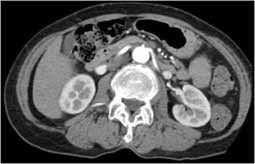

Mri scan > pet scan > ct scan > pregnancy ultrasound scan > other scans and investigations > find the cost of. An mri, by the very nature of the procedure, does not pose any radiation risk. Ct scans can produce detailed images of many structures inside the body, including the internal organs, blood vessels and bones. How much does a ct scan cost? On mdsave, the cost of a ct scan with and without contrast ranges from $320 to $1,869.

Read more about how mdsave works. Ct scans allow physicians to rapidly create detailed pictures of the body allowing them to more easily diagnose problems such as cancers, cardiovascular disease, infectious disease, trauma and musculoskeletal disorders. $10,174.75, including $8,897 for a ct scan of the abdomen. About 100 ct scans pose a high risk of cancer. In new york city, the total cost—including. 5%, more than 22 scans; A ct scan (also called a cat scan) is a noninvasive, painless medical test that helps physicians diagnose and treat medical conditions. Scans that require the injection of iodine, for instance, could run up to $1,000 for the entire procedure.

The average cost of a ct scan in the united states is $3,275, though prices can range from $300 to $6,750. Costs may also vary by veterinarian and geographic location. Ct scans are quick, painless and generally safe. For the group as a whole, the increase in risk was slight — 0.7% above the overall lifetime risk of cancer in the united states, which is 42%. An mri, by the very nature of the procedure, does not pose any radiation risk. How much does a ct scan with and without contrast cost? How much does a ct scan cost? Mri scan > pet scan > ct scan > pregnancy ultrasound scan > other scans and investigations > find the cost of. In new york city, the total cost—including. With a ct scan, the machine. How much do ct scans for pets cost? Read more about how mdsave works. Ct scans are sometimes called cat scans.